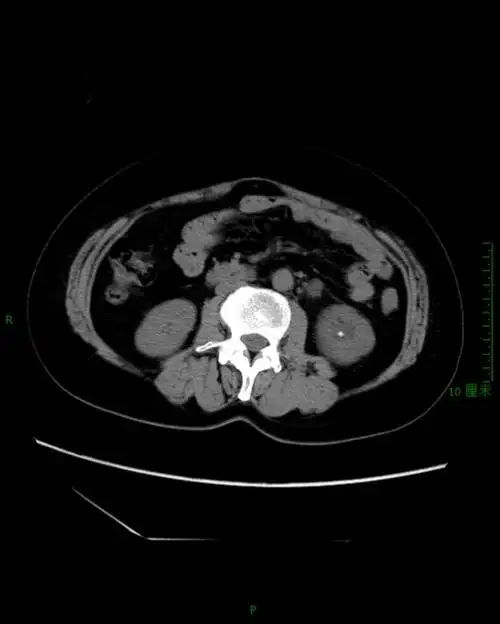

pcnl处理一例无积水的复杂肾结石

ct片上显示肾里塞满了结石

ct影像显示肾脏被巨大结石霸占.长沙晚报通讯员 胡薇华 陈昊 供图

ct右肾结石